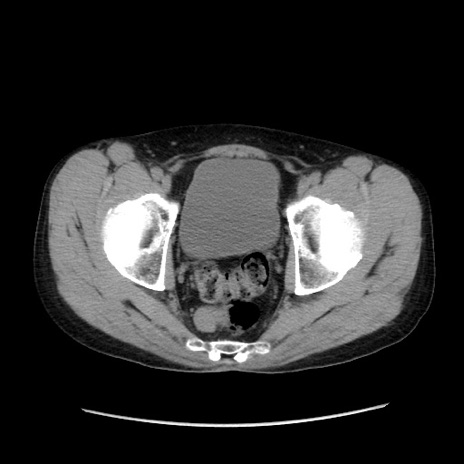

症例37(横断像)

【症例】40歳代 男性

【主訴】腹痛

【現病歴】4時間ほど前に電車に乗車中に臍部上より腹痛出現。徐々に増悪し起立困難となり、救急外来受診。生ものは数日食べていない。今朝お雑煮を食べた。

【身体所見】BT 36.8℃、BP 117/84mmHg、HR 91/min、SpO2 97%、苦悶様、腹部:臍上部広範囲圧痛あり、反跳痛±

【データ】WBC 8100、CRP 0.03